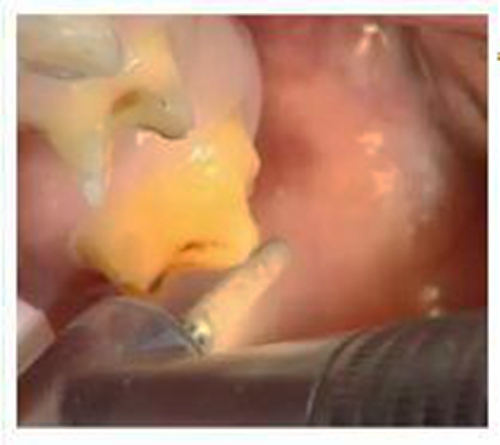

牙體預備是牙科修復中非常重要的一個步驟,如何讓預備更準確,效果更好,就需要牙醫(yī)在操作的過程中掌握操作細節(jié)。

一、預備牙體

預備牙體常用車針:

備牙后需要使用沙粒較細的車針過順,使表面平溜,更易于修復體就位。

備牙注意: